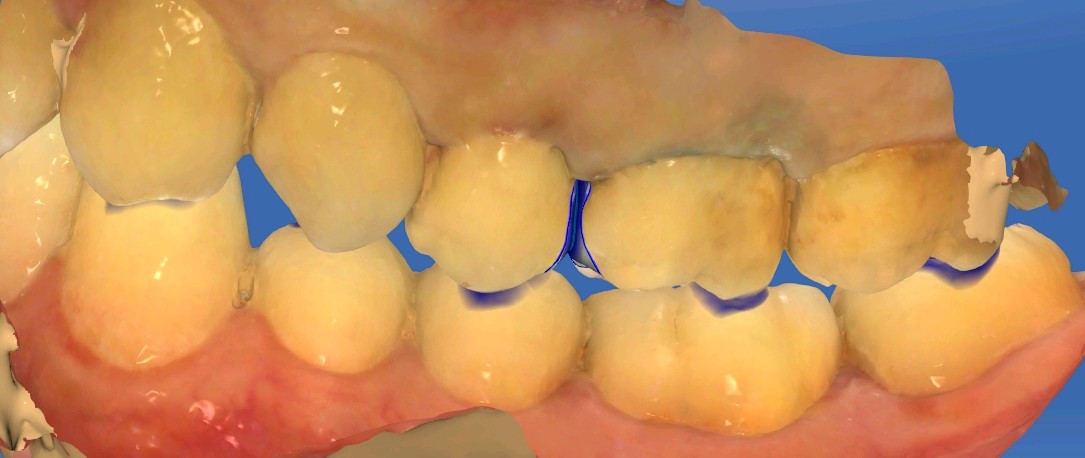

患者男,28岁。主诉左上后牙食物嵌塞。检查发现25、26邻面龋坏,色泽发黑,质硬 冷测正常,余无特殊。治疗计划:去腐后嵌体修复。

图片发自160App

术前